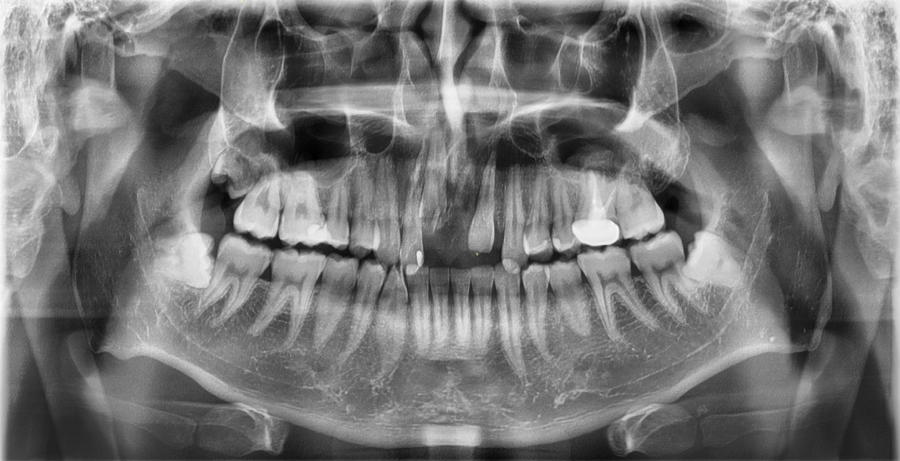

This is an X-ray of a patient who visited with a front tooth that had fallen out after a traffic accident.

In addition to the immediate aftermath of the accident, this image was taken for additional confirmation to check whether there were any changes in the surrounding teeth and jawbone depending on the subsequent progress.

This is a case in which a dislocated front tooth was repositioned and treated using a fixation device.